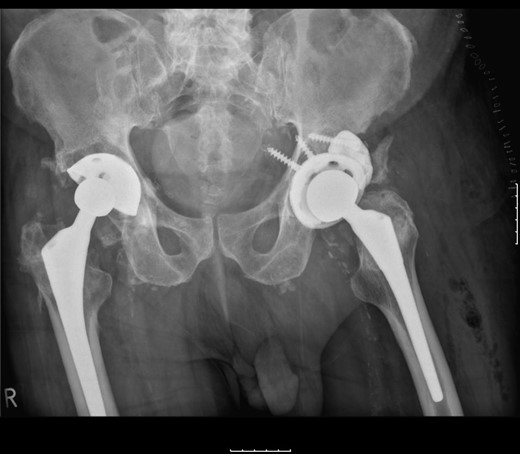

The patient was subsequently scheduled for revision surgery of the acetabular component. Intraoperatively, there was blackening of the periprosthetic tissue and metal debris throughout. The PE liner remained engaged within the acetabular cup with significant wear through its back. The femoral head had migrated superolaterally through the acetabular cup and was articulating with the superior acetabular wall causing bony destruction. The acetabular cup remained well fixed within the acetabulum with good bony ingrowth (Figs 2 and 3).

The acetabular component showing extreme wear-through and metallic fragments.

The femoral stem was kept firm in its proper position. Structural porous titanium acetabular augment (Regenerex™), reinforced with a cancellous allogeneic bone graft, was used to reconstruct the superior acetabular wall. The cup was completely revised using a Biomet® Regenerex Ringloc® multihole 56-mm acetabular cup and a Hi-wall Ringloc-x PE 54-mm liner. The previous 32-mm femoral head was replaced with a Bioball® 36-mm metal head and a Bioball® adapter standard (0 mm) Taper 11/13 (4° 3°), correcting the offset and achieving stability (Fig. 4).

A post-revision radiograph demonstrating a structural graft using the acetabular augment (Regenerex™) and revised cup in situ.